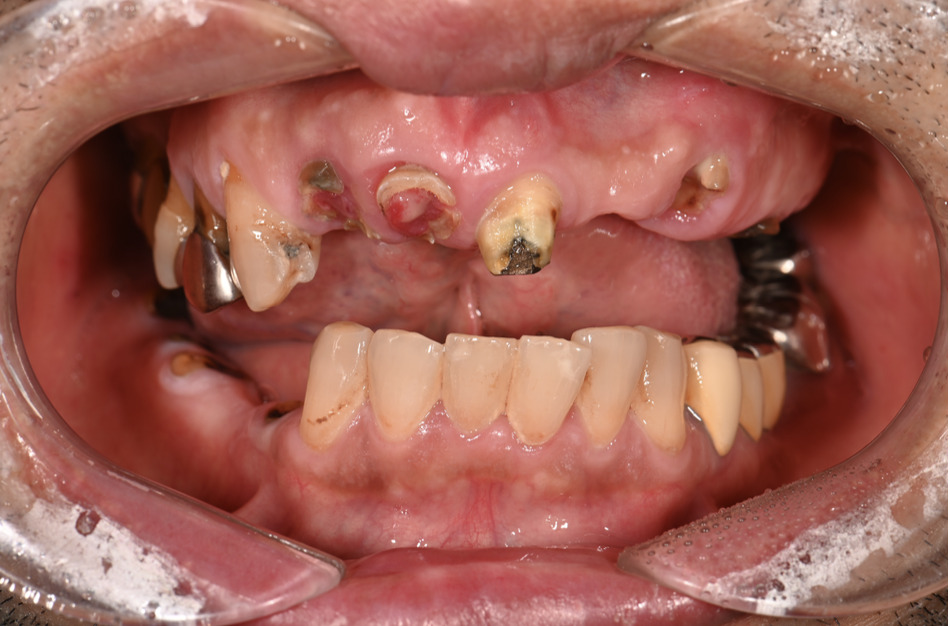

| 主訴 | 全体的にきれいにしたい |

|---|---|

| 治療内容 | 午前中に上下顎共に重度の歯周病、虫歯のため全ての歯を抜歯させていただき下顎はインプラントの土台を3本埋入し歯型を取り午後に上部構造(下顎全ての歯)を装着、上顎は一度総入れ歯を装着させていただきました。 治療が1日で完了しその日のうちに噛めるようになります。 |

| 治療期間 | 2回(1回目に資料取りをさせていただき2回目に下記の全ての治療をさせていただきました。) |

| 治療費 | 250万円 |

| 治療 リスク | 抜歯した部位などに関しては当日痛みが出ますので痛み止めなどを処方させていただきます |